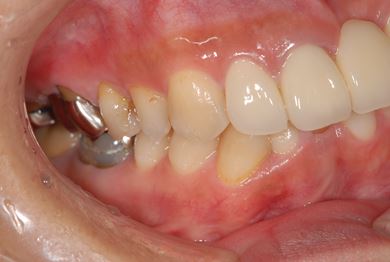

| 性別/年齢 | 女性 / 40歳 | ||||||||||||||||||||||||||||||||

| 主訴 | 前歯のさし歯の部分が目立ってしまい、新しくしたい。痛みも少しある。 | ||||||||||||||||||||||||||||||||

| 治療方針 | 保存不能な歯を抜歯し、セラミック治療にて、機能的・審美的回復を行う。 | ||||||||||||||||||||||||||||||||

| 治療内容 | ジルコニアフレームオールセラミッククラウン7本(オールセラミック用土台3本)、ハイブリッドセラミッククラウン1本、ハイブリッドセラミックインレー1本 | ||||||||||||||||||||||||||||||||